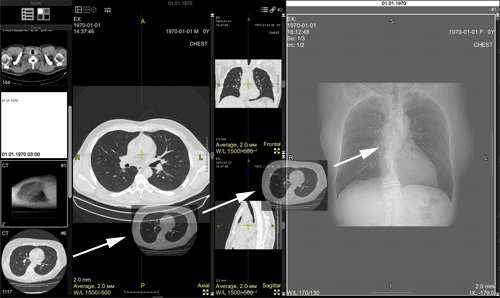

The screen will split into two parts:

The first part will contain the current study,

the second part will be about the next study in the Preview Bar